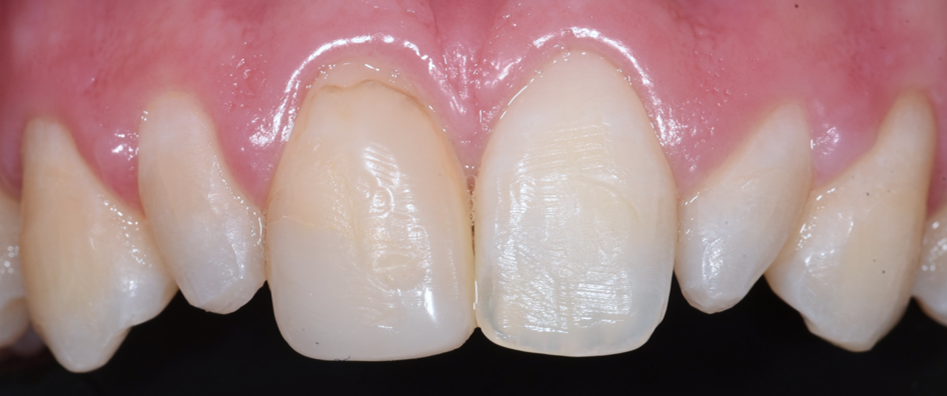

שיקום הפה לפני ואחרי - צילומי שיניים

רופא שיניים מומחה לשיקום הפה | ד"ר חיים אבשלום | השלמת שן לאחר חבלה